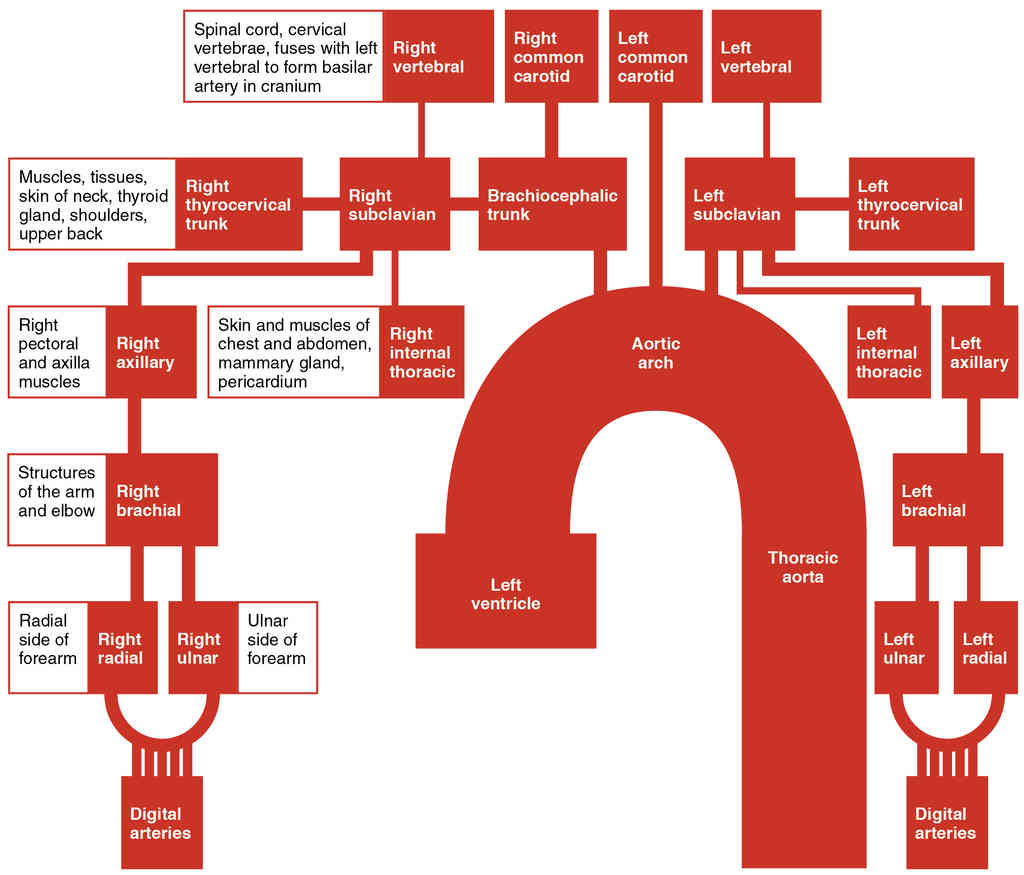

This page is under construction. For now, it is just a resource of the images found in the OpenStax Anatomy and Physiology Handbook. It wil slowly change into a revision tool. Each slide has a number. Use this to refer to the slide. When completed, it will have an unlabelled section, with labelled slides in parallel. On the unlabelled slides, write your answer and use the labelled slide to assess yourself. Keep track by also noting the number on each slide. Improvement at each attempt is important, more so than full marks on a first attempt.